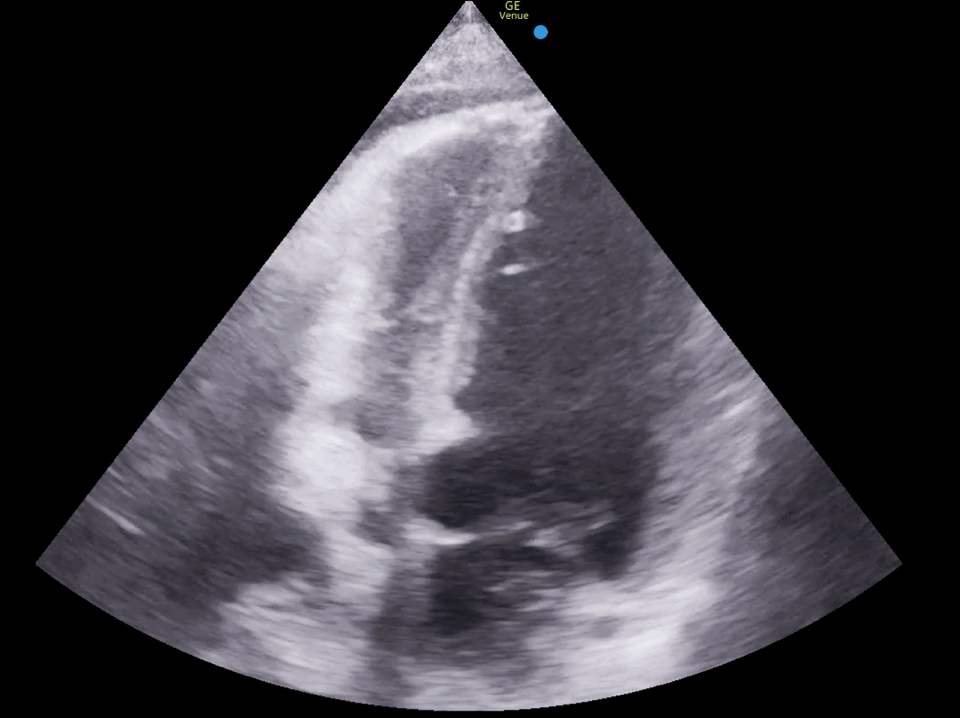

SC view showing large pericardial effusion compromising right ventricular filling: This SC view displays a large pericardial effusion that is significantly compromising the filling of the right ventricle. The large anechoic (black) fluid collection around the heart is exerting pressure on the right side, limiting its ability to fill properly during diastole, which is a critical sign of approaching tamponade.

SC